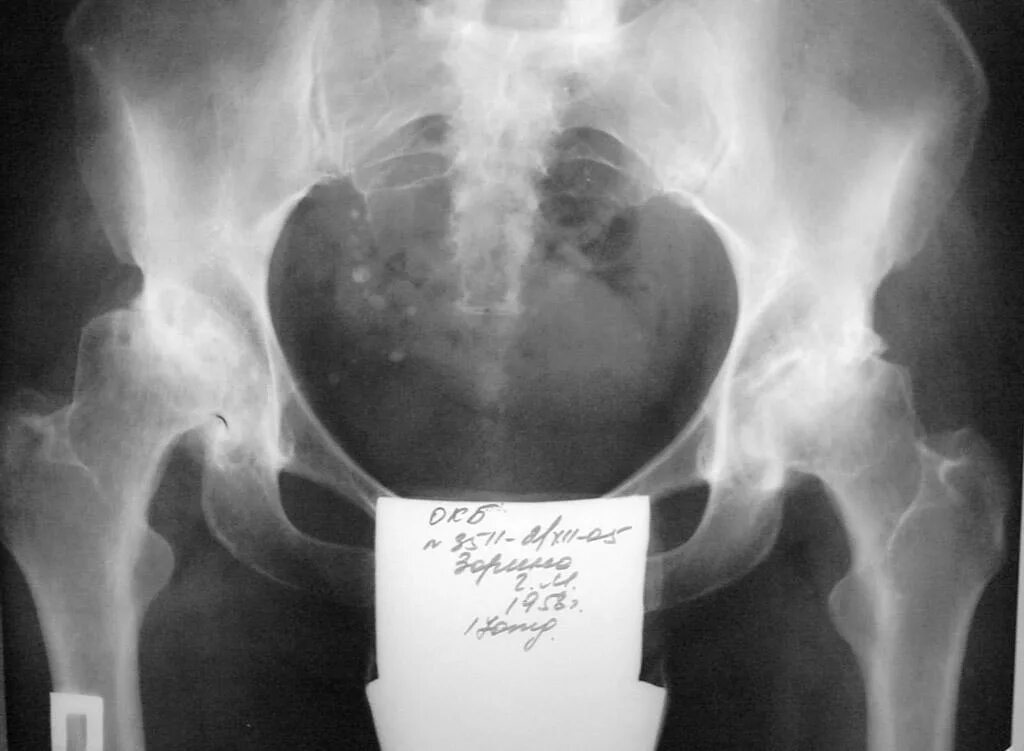

Асептический некроз инвалидность